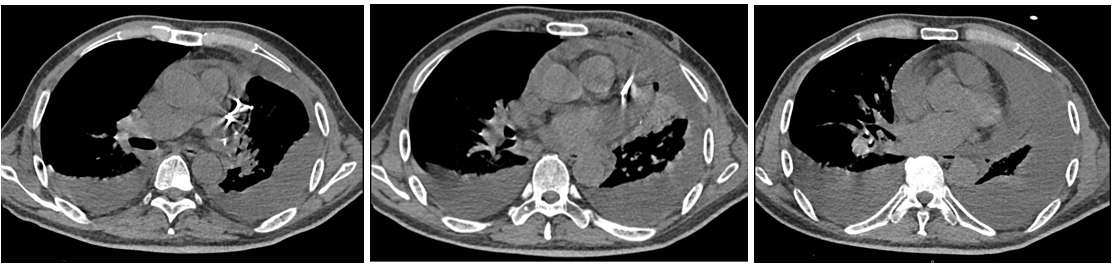

辅助检查

胸部CT显示左侧上叶支气管旁部发现一不规则、边界不清的软组织肿块,大小约为41mm×26mm。增强扫描后,肿瘤呈显著不均匀强化,与肿大的淋巴结粘连且难以区分,部分包裹左上叶支气管,导致管腔狭窄。左上叶肺叶间裂增厚,多个结节灶提示可能存在肺内转移。

新辅助治疗:SBRT方案的剂量为24Gy/3次(每次8Gy),连续3天完成;靶区为仅针对原发肿瘤(GTV),未照射淋巴结;PTV中位体积为152cc(范围20–584cc);化疗方案(每3周一次)为紫杉醇274mg(第1天),顺铂40mg(第1–3天);免疫治疗为替雷利珠单抗(PD-1抑制剂)200mg(第1天,每3周)。

治疗缓解评估:影像学(CT)显示原发肿瘤及叶间淋巴结明显缩小;支气管镜显示左上叶开口通畅,原肿块显著退缩,可见白色坏死组织;疗效评估为PR。

手术治疗:新辅助治疗完成后6周,行VATS辅助左上肺叶切除+肺门及纵隔淋巴结清扫;术中血管解剖清晰,淋巴结清扫顺利;切口小,胸腔镜辅助下完成重建。

术后病理结果:鳞状细胞癌;残留肿瘤细胞为5%;间质成分(纤维化/炎症)为90%;淋巴结为0/13转移;ypT1aN0M0,IA期;疗效评估为MPR。